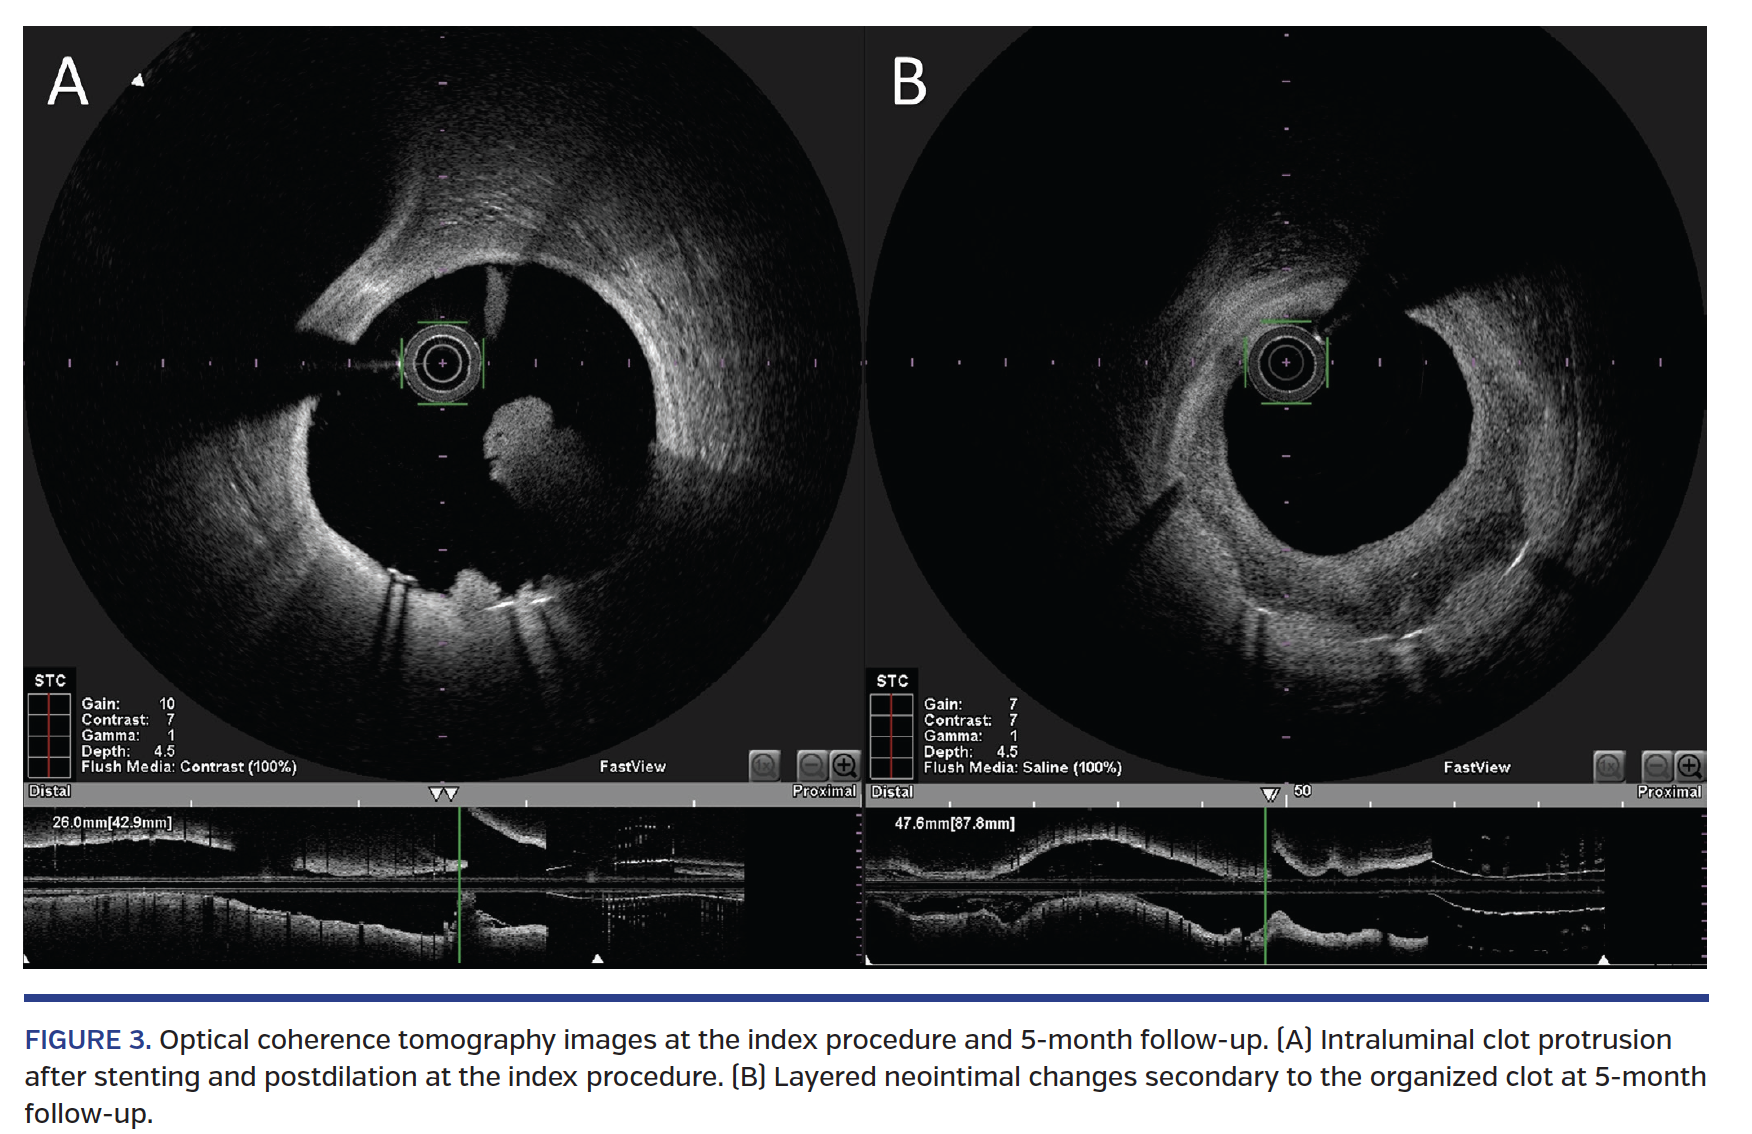

A 37-year-old male presented with self-aborted anterior ST-elevation myocardial infarction. Urgent coronary angiogram showed thrombotic lesion in the proximal left anterior descending (LAD) artery (Figure 1). Multiple passes of aspiration thrombectomy retrieved a large amount of red thrombi. A drug-eluting stent was deployed in view of residual stenosis and clots (Figure 2, Video 1). Final OCT showed intraluminal clot protrusion at the proximal stented segment and proximal stent edge (Figure 3A, Video 2). The protruding clot was left for medical therapy with double antiplatelet agents because of the absence of flow limitation and edge dissection.

The patient remained clinically asymptomatic and scheduled follow-up coronary angiogram with OCT was performed 5 months after the index procedure. Follow-up OCT study showed the protruding clot had resolved with residual layered neointimal pattern at the proximal stent edge (Figure 3B, Video 3).